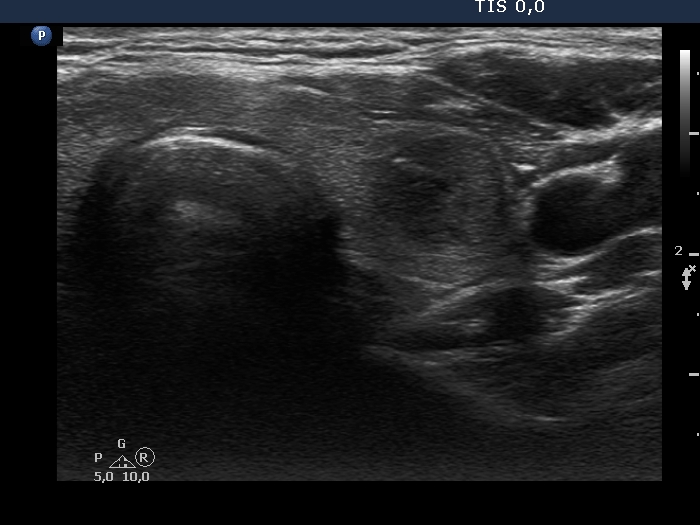

First examination (first row of images):

Clinical presentation: A 39-year-old woman was referred for evaluation of a nodule detected on ultrasound screening. Cytology resulted in benign lesion. The aTPO level proved to be elevated.

Palpation: a firm lesion in the left lobe.

Functional state: euthyroidism (TSH 2.65 mIU/L, anti-TPO > 1300 U/mL).

Ultrasonography. The thyroid was echonormal and has several small, moderately hypoechoic areas corresponding to thyroiditis. There was a hypoechoic nodule in the left lobe. The lesion had microcalcifications, presented with irregular, lobulated margins and showed a combined perinodular and intranodular vascularity.

Considering the ultrasound presentation, we performed cytology which resulted in non-diagnostic result.

Suggestion: ultrasound in a year.